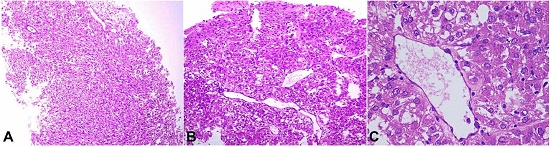

Therefore, in view of tumor unresectability, a biopsy was taken and the resection was suspended. The microscopic examination showed a varied morphology with short fascicular arrangement of spindle shaped tumor cells, with intervening thin walled vascular channels (Figure 2A), and nests and lobules of tumor cells with epithelioid morphology. These epithelioid tumor cells appeared to be more centered on dilated thin walled vascular channels (Figure 2B). The tumor cells showed moderate nuclear pleomorphism with vesicular chromatin, prominent nucleoli and moderate to abundant amounts of clear to pale eosinophilic cytoplasm (Figure 2C).

Scattered mitotic figures and a few interspersed multinucleated tumor cells were also seen. A possibility of RCC with sarcomatoid differentiation was considered. However, on immunohistochemistry, the tumor cells showed immunoreactivity for Melan A (Figure 3A) and SMA (Figure 3B) and were negative for PAX-8, Pan-Cytokeratin, Myogenin, CD117, CD34, CK7, PAX-8 and HMB-45.

In view of classical morphology and supporting immunohistochemistry findings, a diagnosis of EAML was considered. Preoperative radiological diagnostic consideration of RCC was excluded by appropriate immunohistochemical results. The patient was discharged after appropriate supportive care and counselling. Once the histopathological diagnosis was made, the case was discussed at a multi-disciplinary team meeting, and possible treatment modalities were discussed. Subsequently, a telephonic conversation with the patient’s relative was made. However, the patient refused to come to the hospital for any treatment. Finally, the patient succumbed to her illness after 2 and half months.